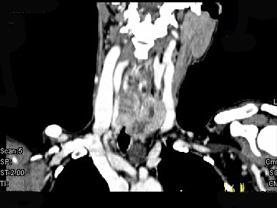

问题 女,50岁,左下颈部扪及一质硬、表面高低不平的包块,约半年,肿块逐渐增大,现感吞咽困难。如图所示CT诊断为 ( )

选项 A、甲状腺原发淋巴瘤 B、颈部神经鞘瘤 C、食管癌 D、喉癌 E、甲状腺癌

答案 E